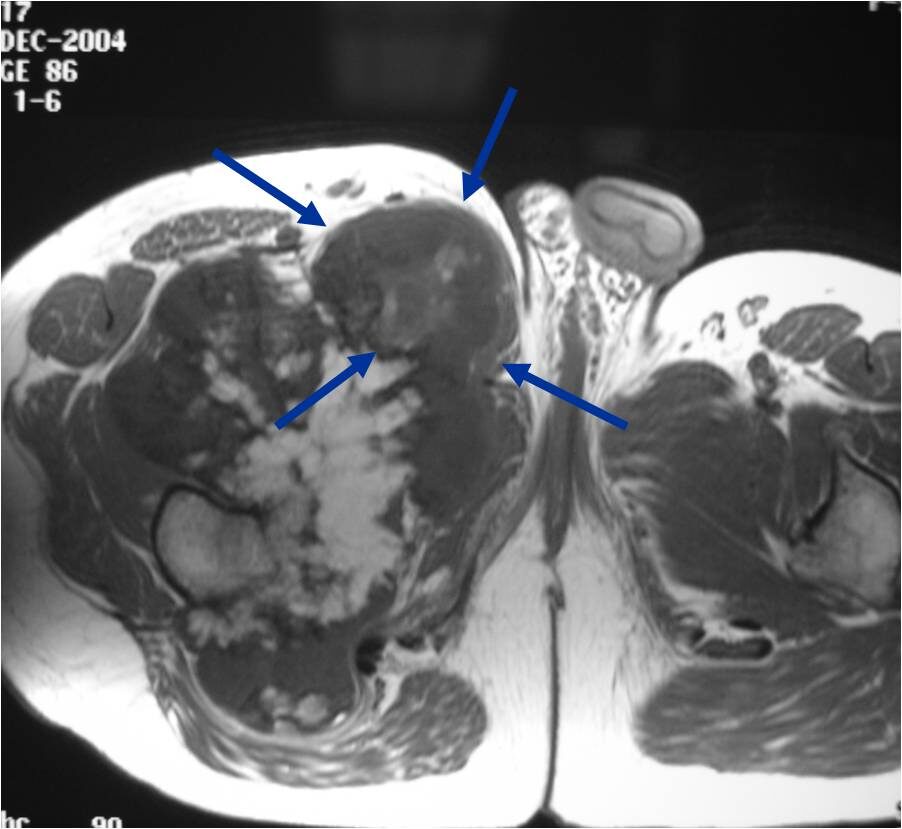

MRI: Secondary Chondrosarcoma of Proximal Femur: Thick Cartilage Cap (>2cm)

- Best test for evaluating thickness of cap and surrounding bursa

- Intermediate T1W Images

- High Intensity T2W Images because of fluid content

- Cartilaginous cap thickness greater than 2cm

- Cortical destruction

- Backgrowth of the cartilaginous cap into the stalk or medullary canal

- Lysis of calcifications in cap